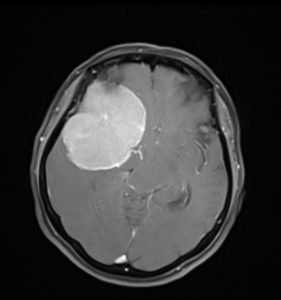

Η μετεγχειρητική αξονική τομογραφία εγκεφάλου δείχνει αφαίρεση της βλάβης χωρίς παρουσία επιπλοκών, και κυρίως χωρίς κάποιο έμφρακτο από τα εμπλεκόμενα αγγεία. Η ιστολογική εξέταση ανέδειξε μηνιγγίωμα, WHO Grade I.